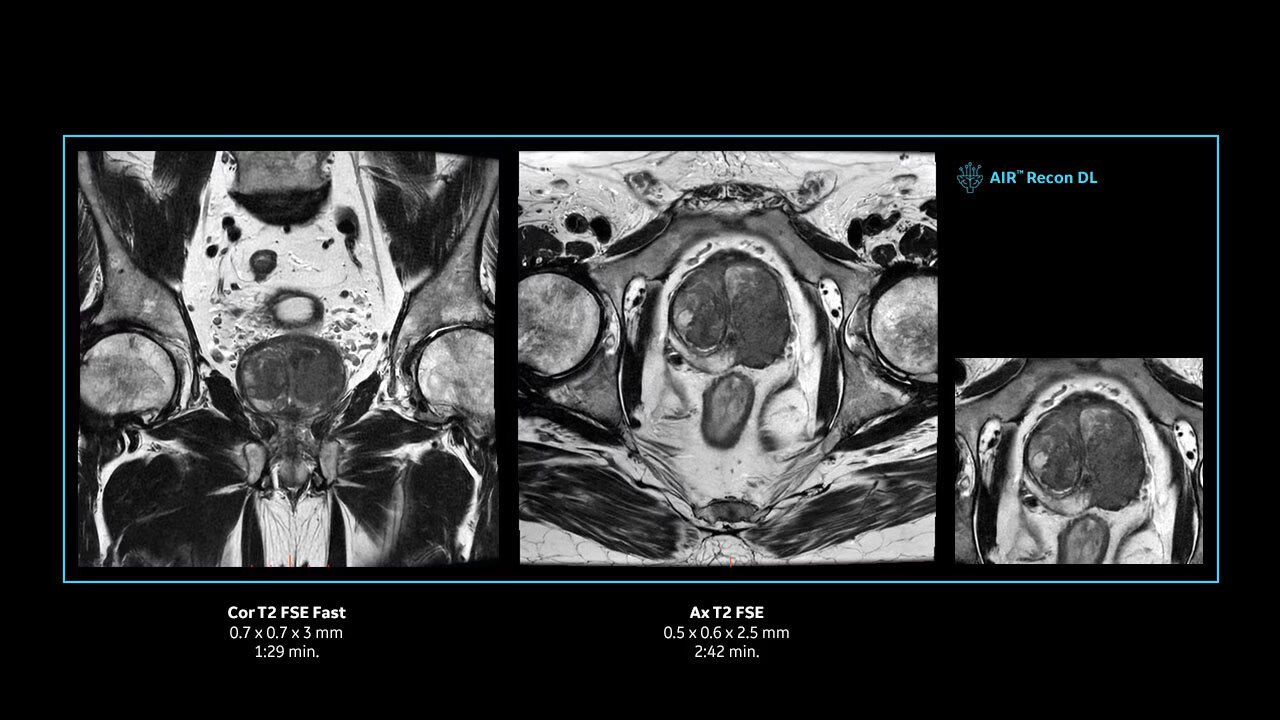

Achieve pin-sharp image quality with pioneering AIR™ Recon DL AI technology.

With access to the latest advanced AI technology, you can scan all anatomies and achieve pin-sharp images. Our pioneering deep learning-based reconstruction algorithm AIR Recon DL accelerates scan time and puts patients at ease.